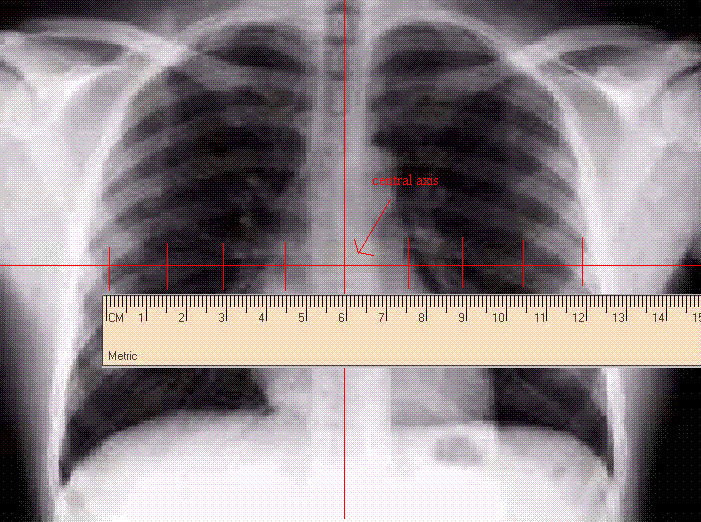

You need to cut a block. The target to tray distance is already set on the block cutter. The Simulation Technologist forgot to write down the target to image distance. The film has hash marks that represent a 1 cm scale at a distance of 100 cm.

There are a number of ways to calculate this. One way is to take 8.0 cm represented on the film and with a ruler measure a distance of 12.0 cm. What is the target to image distance?

Your target to image disance would be 150 cm.

The 100 cm is your target to isocenter distance and, in this case the hash marks represent 1 cm at a distance of 100 cm. If you count out 9 hash marks, this correlates to 8 cm at 100 cm distance. If you measure the 9 hash marks and get an actual measurement of 12 cm on the film, then you can use the above proportion to solve for x and come up with the correct target to image distance.